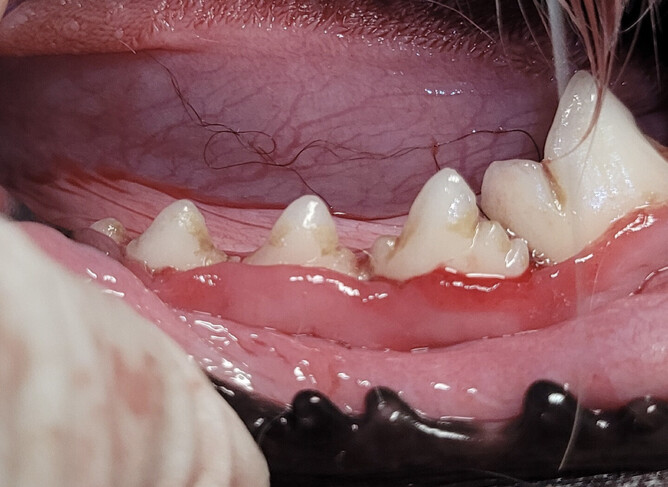

From the outside their teeth might look clean, white, and free from any obvious tartar or inflammation. But beneath the gum line can hide problems like infection, or even bone loss and furcation exposure – signs that periodontal disease is happening that would otherwise go undetected.

At Vet Clinic Morrinsville, we take dental x-rays as part of every full dental procedure. It helps us find things like:

Bone loss around teeth

Root abscesses or infections

Hidden fractures or retained roots

Tooth resorption and other changes below the gum line